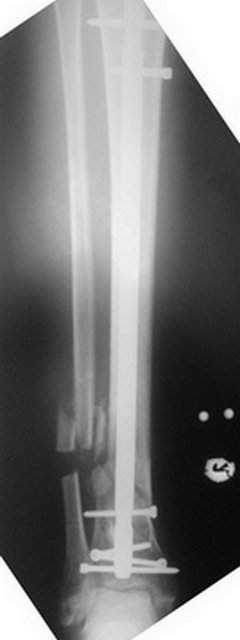

[Ortho] ложный сустав обеих костей правой голени

Вложение не в текстовом формате было извлечено…

Имя     : r_postop_lat.jpg

Тип     : image/jpeg

Размер  : 15027 байтов

Url     : http://weborto.net:8080/pipermail/ortho/attachments/20110817/d4952754/attachment-0005.jpg